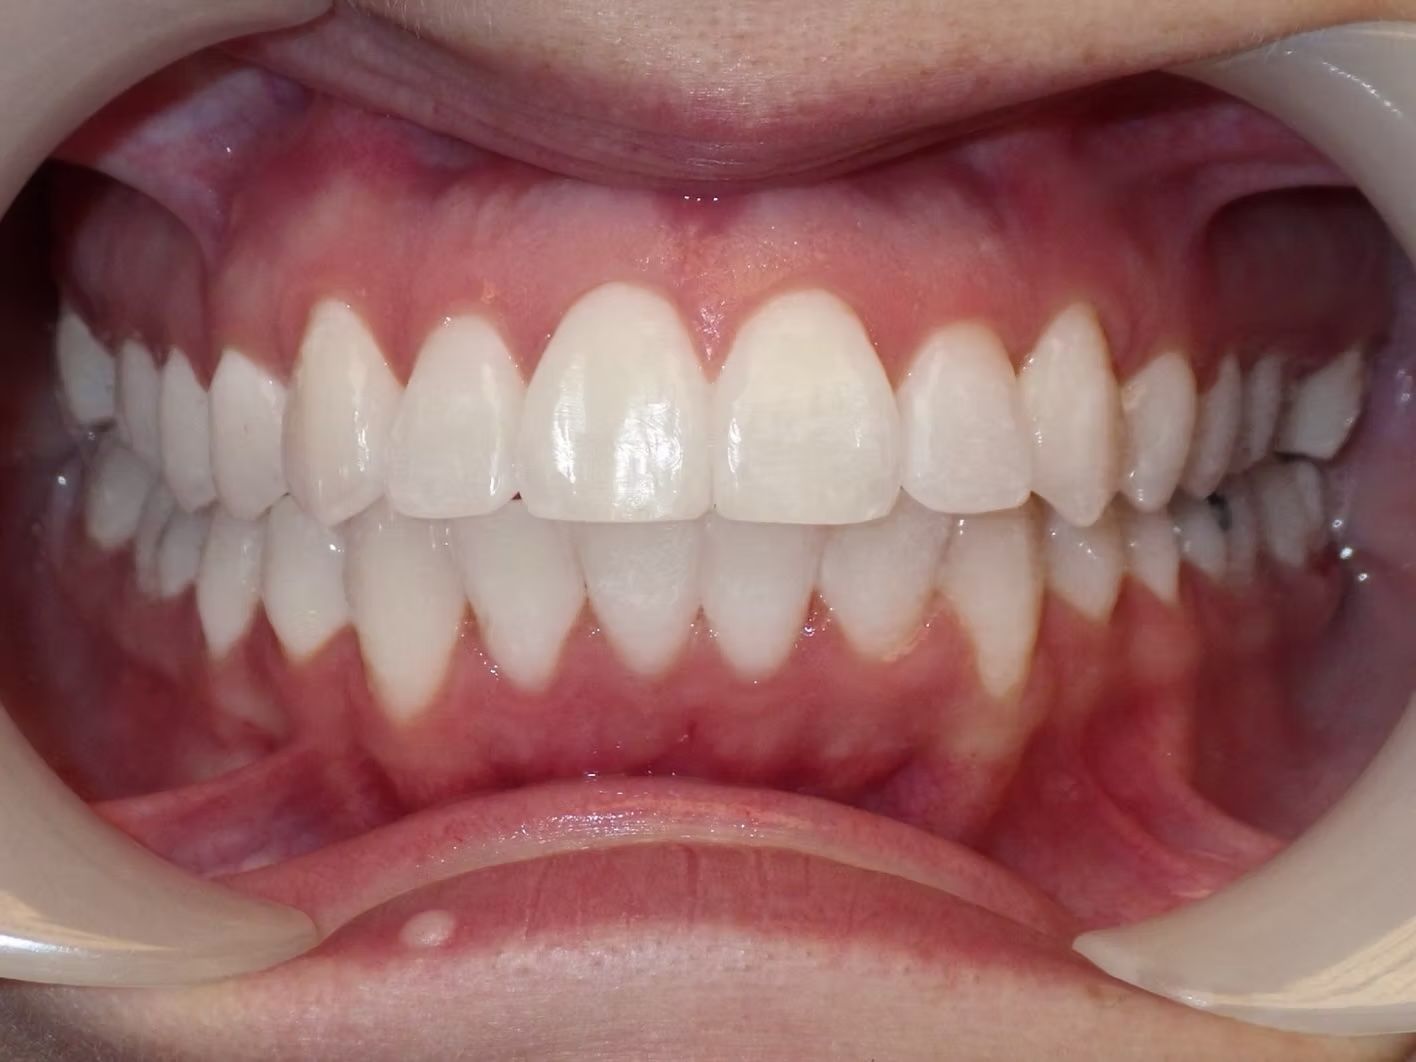

Emily

Emily didn't like how her top teeth were turned in and the lower teeth were crowded. Her bite was slightly off on both sides. Emily just needed upper and lower braces to correct her dental alignment and some rubber bands to correct the bite. She absolutely loves her teeth now!